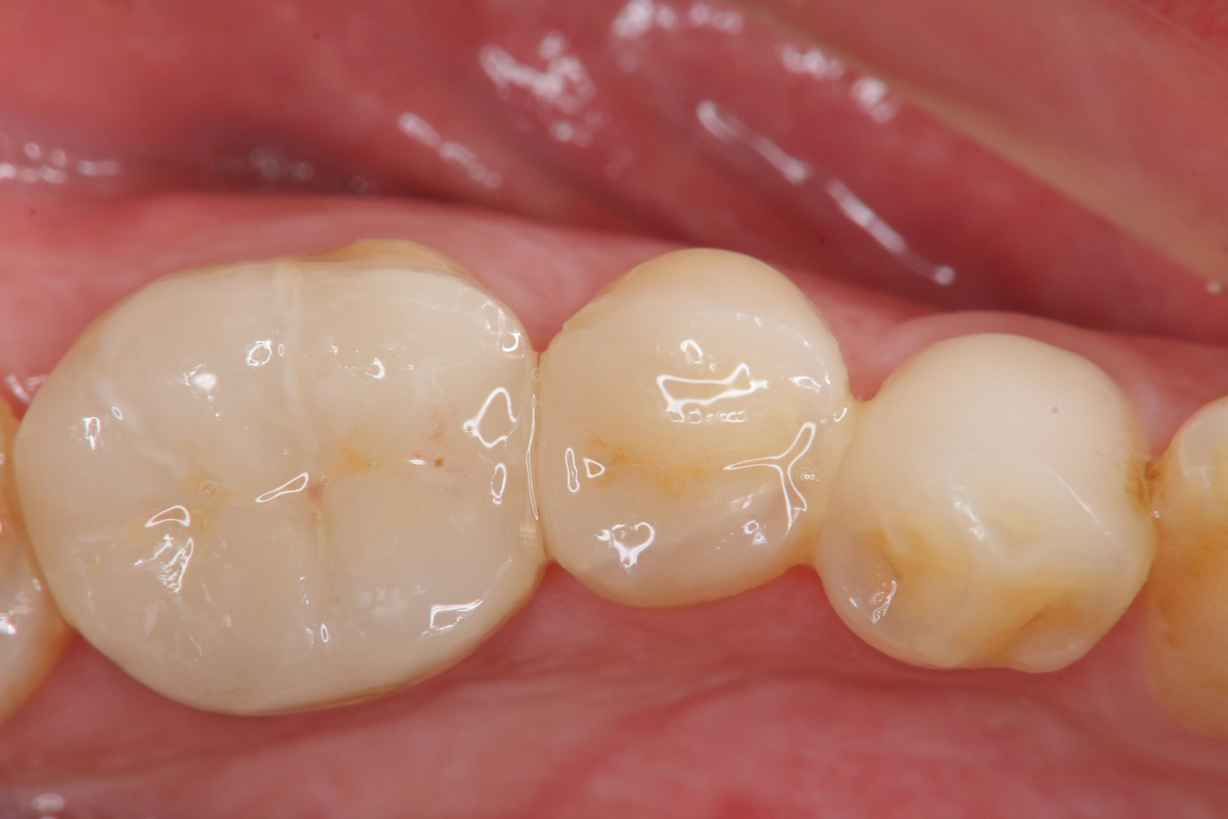

治療後,口內照相追蹤